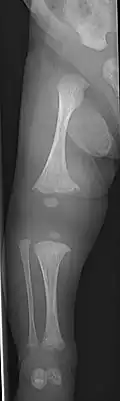

- Type V – Having the same clinical features as type IV, it can be clinically distinguished by observing a "mesh-like" appearance to a bone biopsy under a microscope. Type V can be further distinguished from other types of OI by the "V triad": an opaque band (visible on X-ray) adjacent to the growth plates; hypertrophic calluses (abnormally large masses of bony repair tissue) which form at fracture sites during the healing process; and calcification of the interosseous membrane of the forearm,[50] which may make it difficult to turn the wrist.[1]: 429 Other features of this condition may include pulled elbow, and, as in other types of OI, long bone bowing and hearing loss.[64] Cases of this type are caused by mutations in the IFITM5 gene on chromosome 11p15.5.[64][49] The separation of type V from type IV OI, its clinical type, was initially suggested even before its genetic cause was known, by Glorieux et al. in 2000.[50][65] Type V is relatively common compared to other genetically defined types of OI—4% of OI patients at the genetics department of the Brazilian Hospital de Clínicas de Porto Alegre were found to have it.[66]